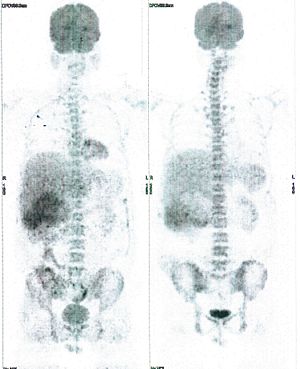

Below are some of the cases, from more than 80 cases we have treated so far with good results. When reading the PET/CT scans, the picture on the left is before treatment, and the picture on the right is after treatment. The intensity of black represents the activity of the cancer, but some black areas are not cancer: brain, heart, radioactive urine in bladder. For the heart, the intensity of black depends on the number of hours of fasting: if more than 10 hours, the heart is not even black, but if fasting is less than 6 hours, it is very black. The intensity of black in the brain can be variable in different scans depending on the brain activity at the time of the scan. The intensity of black in the radioactive urine can also be variable due to the hydration of patients and the time of injection of diuretic.

CASE NO: 3 (PROSTATE CANCER)

A middle-aged man with castration resistant prostate cancer, having failed all currently available cancer treatment, was very weak, and getting worse every day. The PET/CT scan showed he had massive bone metastases. After a few treatment, all the bone metastases went into remission. About 6 months later, he is still in remission.

CASE NO: 4 (PROSTATE CANCER)

A middle-aged man with castration resistant prostate cancer and massive bone metastases, failed all currently available cancer treatment, including with the new and expensive drug XTANDI. After a few treatment, most of the bone metastases went into remission, and the remaining ones are less active. Treatment will continue. Cases no: 3 and 4 show that terminal prostate cancer today can be cured with our new cancer treatment.